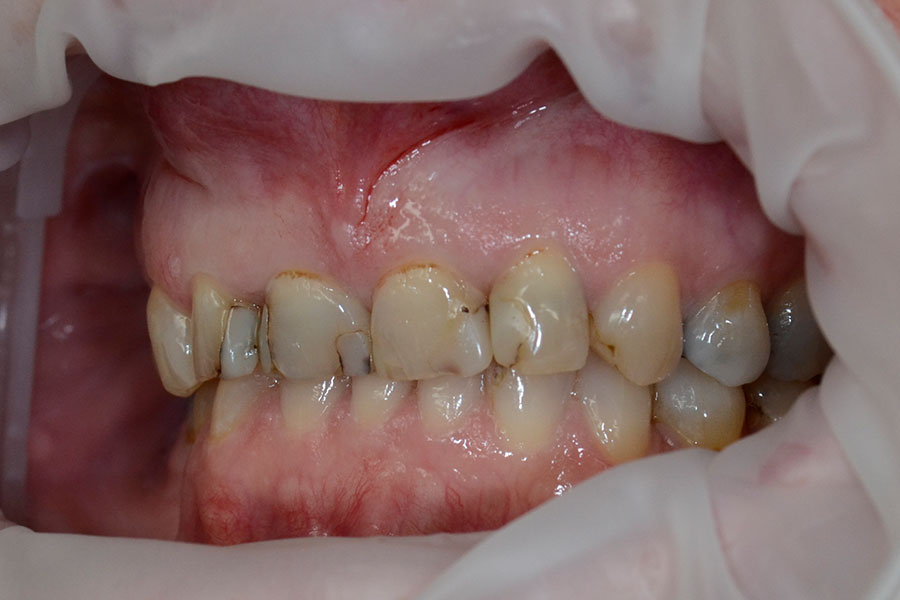

Replacing Unesthetic Fillings

The following cases had stained and failing white fillings. Interestingly one person even had very old gold inlays in their front teeth.

They were replaced with esthetic ceramic veneers. As seen in these images changes to shape and size within limits can also be achieved along with the color.